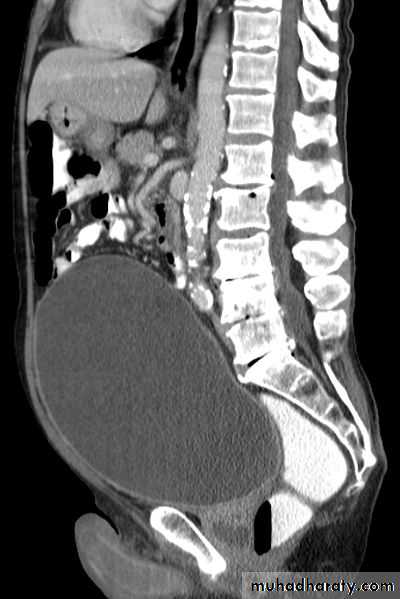

Boo over time will result in increase in the intravesical voiding pressure (>80 cm H2O), bladder muscle hypertrophy (trabiculation, sacculation and diverticulum formation).

High pressure may transmit to the upper tract causing hydroureter, hydronephrosis and renal insufficiency.

U/S:TRUS: BPH, vesical stone, residual urine and hydronephrosis.

IVU